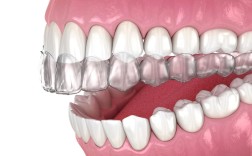

牙齿矫正是通过外力引导牙齿、颌骨及周围组织改建,最终实现咬合功能与面部美观协调的医疗过程,矫正器作为核心工具,根据作用机制可分为固定矫正器、活动矫正器及功能矫正器等,其中功能矫正器因其在调节颌骨发育、改善口腔肌功能方面的独特优势,在儿童及青...